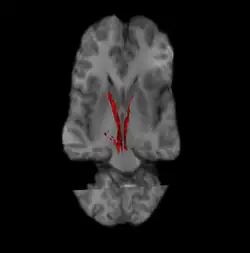

Nigrostriatal pathway

Nigrostriatal pathway (Left and Right in red).